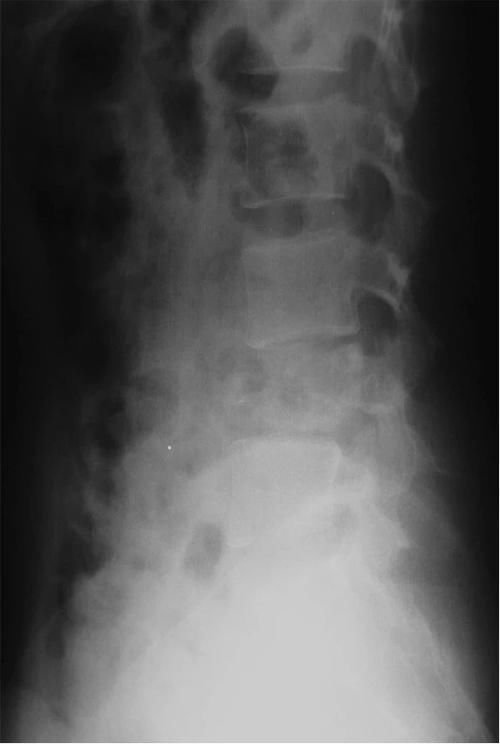

Case14:M,6y;双侧髋部疼痛1月余,加重伴不能行走半月。

文章插图